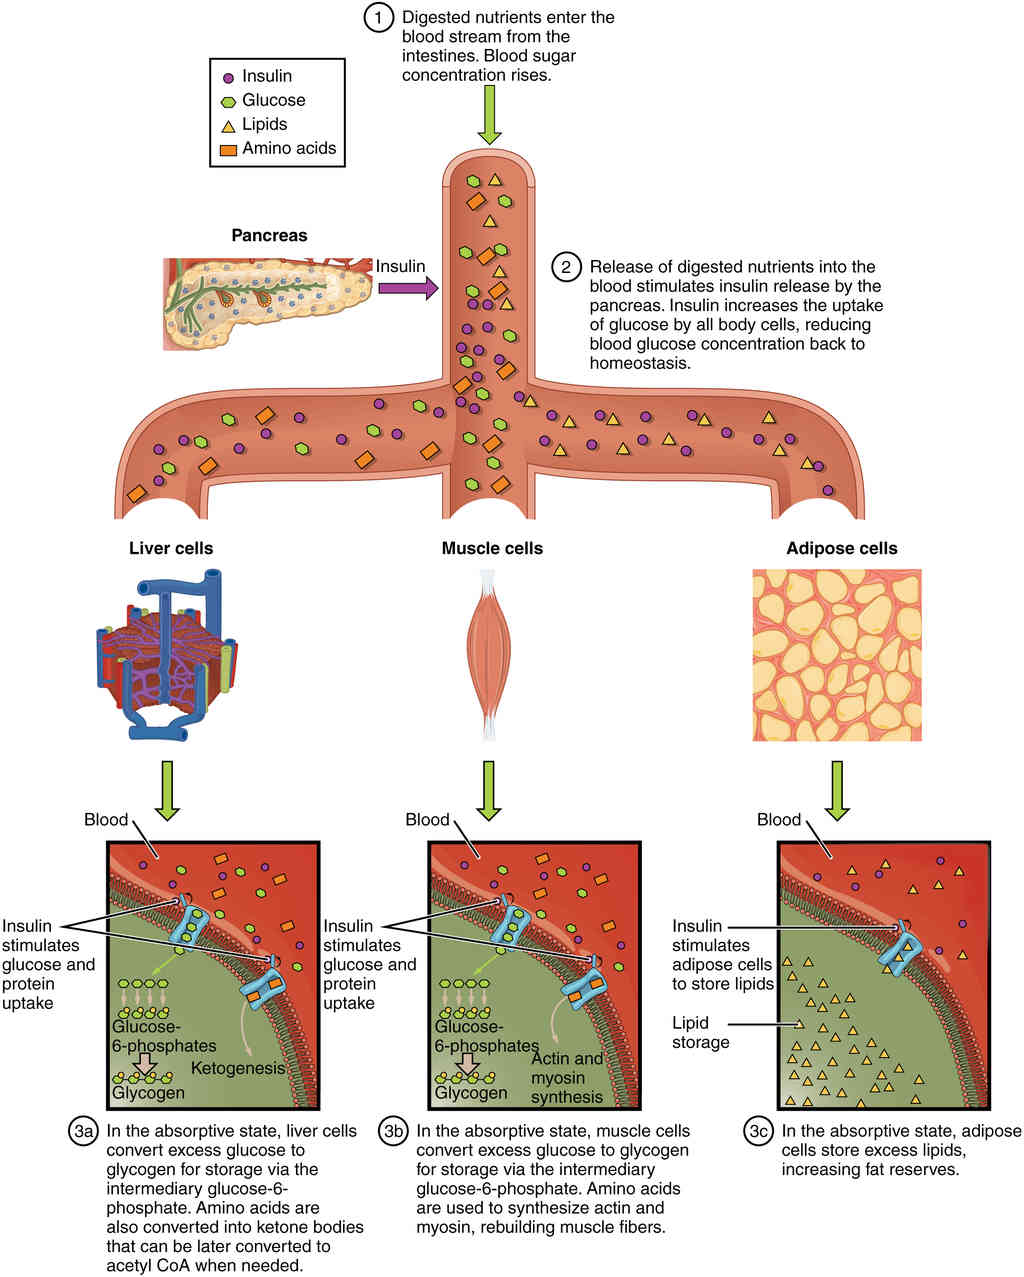

This page is under construction. For now, it is just a resource of the images found in the OpenStax Anatomy and Physiology Handbook. It wil slowly change into a revision tool. Each slide has a number. Use this to refer to the slide. When completed, it will have an unlabelled section, with labelled slides in parallel. On the unlabelled slides, write your answer and use the labelled slide to assess yourself. Keep track by also noting the number on each slide. Improvement at each attempt is important, more so than full marks on a first attempt.